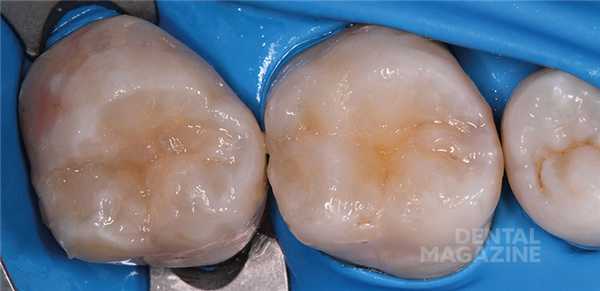

После восстановления и полимеризации дентинного слоя (Ceram•X™ duo+) один за другим были внесены оттенки основной и поверхностной эмали (Esthet•X® HD A2 и АЕ) общей толщиной 1,5—2 мм, тщательно адаптированы к поверхности с разметкой приблизительных контуров без последующего отверждения (рис. 6) .

Наступает очередь окклюзионного ключа (рис. 7) .

Для предупреждения возможного склеивания следует нанести на поверхность силикона небольшое количество адгезива. Ключ накладывается на зуб и медленно прижимается. После того как силиконовый оттиск встанет на свое место, нужно медленно его снять легкими раскачивающими движениями. Не следует торопиться и пытаться извлечь ключ одним рывком: это приведет к деформации композитного материала. Если все сделано правильно, порция неотвержденного эмалевого композита должна принять точную форму исходной жевательной поверхности (рис. 8) .